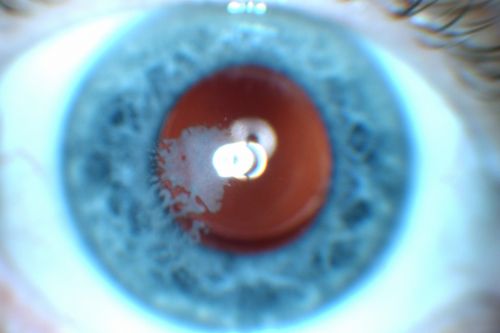

Post Lasik Epithelial Ingrowth

58-year-old man had a vitrectomy for a macular pucker in the right eye almost two years ago.  His vision was good after his cornea surgeon removed the cells from his flap but then recently the cells have regrown and his vision has declined again.

OD is 20/100.